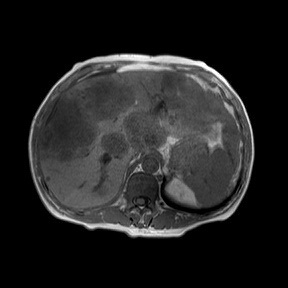

一位46岁男性患者,间歇性大便出血1年余,以为是痔疮,自行到药店买了痔疮药用,便血时断时续。后来体重明显下降,才在家人的建议下来温州医科大学附属第一医院结直肠肛门外科门诊就诊。问诊之后,医生给他做了直肠指检,基本明确是直肠癌而不是痔疮。接下来又安排他做了结肠镜检查和胸腹盆腔增强CT及直肠、肝脏MRI检查,结果发现是直肠癌伴肝转移,属于晚期。患者就这样因为自己的不重视,耽误了病情,非常可惜。

▲ 患者肝脏磁共振显示肝脏布满肿瘤